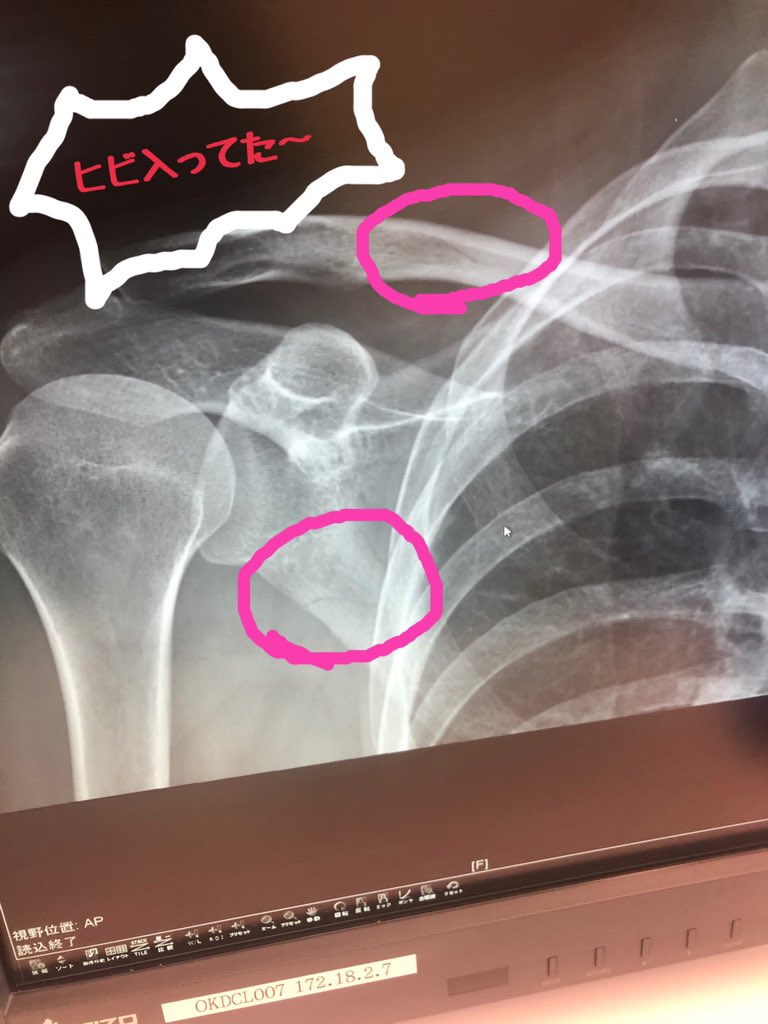

برچسب 鎖骨にヒビ در توییتر